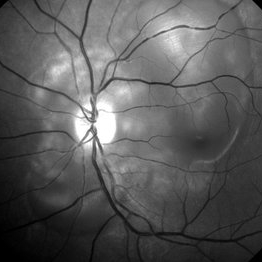

Preeclampsia in a 30-Year-Old - Red Free Photograph - LE

Nov 25 2015 by Roy Schwartz, MD

A 30-year-old presented with central scotoma and blurred vision a day following C-section for preeclampsia.

Photographer: Galit Yair Pur

Condition/keywords: blurred vision, central scotoma, preeclampsia